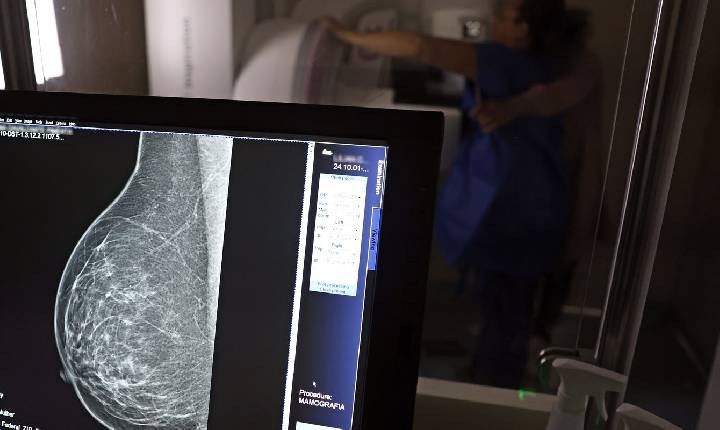

Nova lei reforça direito a três folgas por ano para exames preventivos

Benefício é exclusivo para empregados no regime da CLT. Empresas passam a ser obrigadas a divulgar essa informação.

Uma nova lei, publicada nesta segunda-feira (6), reforça o direito do trabalhador com contrato via Consolidação das Leis do Trabalho (CLT) de se afastar até três dias por ano para realizar exames preventivos de câncer, em desconto salarial.

O direito já estava incluído na CLT desde 2018. A partir de agora, as empresas passam a ser obrigadas a divulgar essa informação, além de outras relacionadas a campanhas oficiais de vacinação contra o HPV e sobre o acesso a serviços de diagnósticos de cânceres de mama, próstata e de colo do útero.

O texto estende o uso das folgas também para a realização de exames preventivos do HPV, além dos de câncer que já estavam previstos na legislação anterior. A a Lei 15.377 foi sancionada pelo presidente Luiz Inácio Lula da Silva, e publicada na edição do Diário Oficial da União (DOU).   >> Siga o canal da Agência Brasil no WhatsApp

Créditos (Imagem de capa): © José Cruz/Agência Brasil